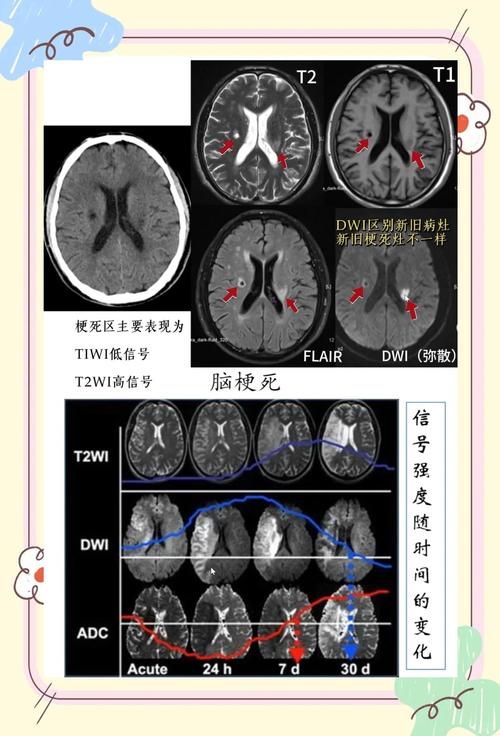

头颅MRI + DWI(弥散加权成像):

- 优点: 这是目前诊断早期脑梗死最敏感、最准确的方法,在发病后几十分钟到2小时内,MRI就能显示出缺血坏死的病灶,是诊断脑梗的“金标准”。